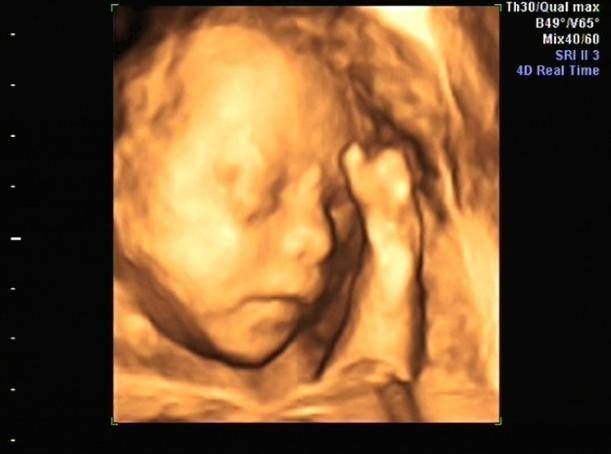

各位孕妈及家属:这就是孕妈做四维检查时,医生不让陪同人员入内的原因。陪同人员也不要着急,你安静在等候区等候孕妈检查出来,相信每一个医生都会用心为孕妈做好检查和服务。